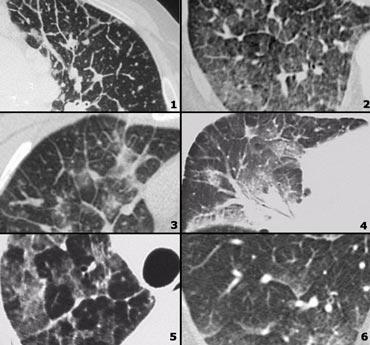

Đây là một trường hợp sarcoidosis phế nang.

Hãy cuộn qua các hình ảnh.

Hình ảnh trông giống như tăng tỷ trọng dạng kính mờ, nhưng khi quan sát kỹ hơn có thể nhận thấy rằng sự tăng tỷ trọng này là kết quả của nhiều nốt nhỏ tập hợp lại.

Cũng lưu ý hạch to rốn phổi.

Sarcoidosis phế nang (2)

Bên trái là bệnh nhân nữ 47 tuổi với triệu chứng ho khan, khó thở nhẹ và xét nghiệm máu bình thường.

Bệnh nhân được chụp X-quang ngực và điều trị kháng sinh.

Phim kiểm tra được chụp lại do bệnh nhân không cải thiện.

Phim X-quang ngực đầu tiên cho thấy đông đặc hai bên ở thùy dưới (mũi tên), ban đầu được diễn giải là nhiễm trùng.

Sau hai tuần điều trị kháng sinh, không có cải thiện.

Chẩn đoán phân biệt lúc này bao gồm u ác tính (ung thư phế quản phế nang hoặc u lympho), viêm phổi tăng bạch cầu ái toan, viêm phổi tổ chức hóa, bệnh Wegener hoặc một thể không điển hình của sarcoidosis.

Tiếp tục với hình ảnh HRCT.

Hãy cuộn qua các hình ảnh bên trái.

Có nhiều vùng đông đặc.

Các dấu hiệu kèm theo bao gồm hạch to rốn phổi và trung thất.

Chẩn đoán phân biệt trên hình ảnh CT về cơ bản giống như trên X-quang ngực.

Kết quả mô bệnh học xác nhận sarcoidosis phế nang.

Chỉ có một gợi ý duy nhất cho chẩn đoán, đó là sự hiện diện của các nốt nhỏ có thể nhận thấy ở hình 3, nhưng rất khó quan sát.

Trường hợp này minh họa rõ ràng rằng sarcoidosis thực sự là “kẻ bắt chước vĩ đại”.

Do đó, sarcoidosis cần được đưa vào danh sách chẩn đoán phân biệt của chúng ta!